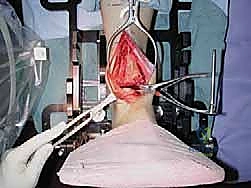

2. الوصول الجراحي الدقيق

يقوم الدكتور هطيف بعمل شق جراحي دقيق في الجزء الأمامي من الكاحل. بفضل خبرته في الجراحة الميكروسكوبية، يتم إبعاد الأوتار والأعصاب والأوعية الدموية بحذر شديد لحمايتها من أي ضرر.